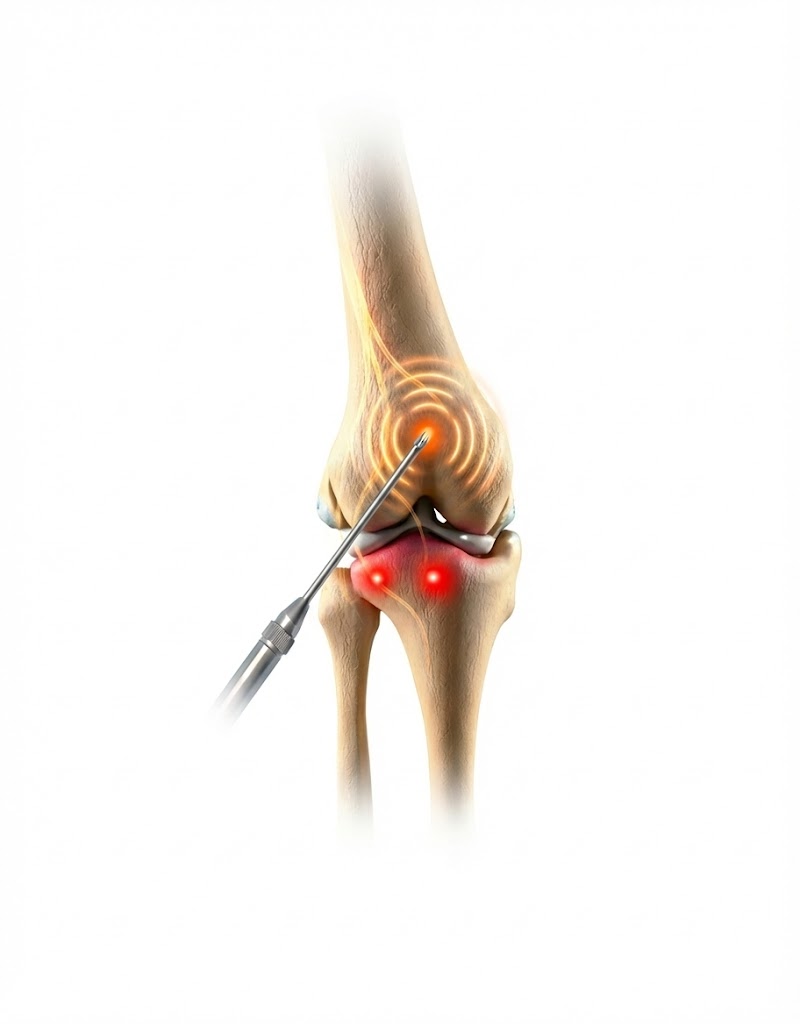

The procedure is performed in two precise stages to ensure the best possible outcome:

- The Diagnostic Block: To confirm that the genicular nerves are the primary source of your pain, a small amount of local anesthetic is injected near the nerves. If you experience significant temporary relief, you are a candidate for the ablation.

- Image Guidance: Using real-time X-ray (fluoroscopy), Dr. Ram precisely positions specialized needles near the sensory nerves of the knee.

- Thermal/Cold Ablation: A small amount of radiofrequency/cold energy is passed through the needle, creating a heat/ice lesion on the nerve.

- Signal Interruption: This “stuns” the nerve, preventing it from sending pain messages. The nerve remains intact, but its ability to transmit pain is deactivated.

- Immediate Recovery: The procedure takes about 30–45 minutes, and patients can typically walk out of the clinic immediately after.